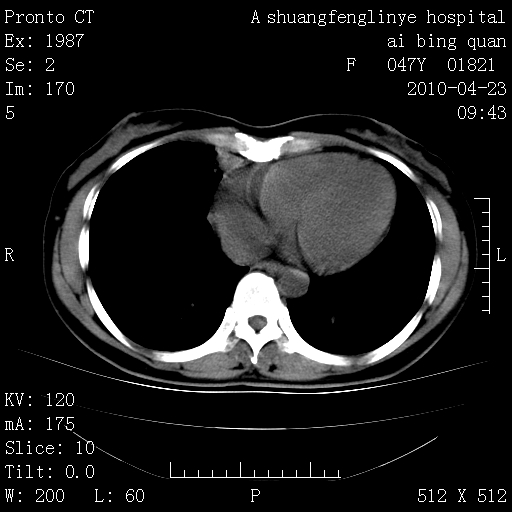

标题: CT25944:胸痛、气短、前几日高烧!肺Ca?请会诊! [打印本页]

标题: CT25944:胸痛、气短、前几日高烧!肺Ca?请会诊!

左侧乳腺低密度灶

双肺多发结节,部分密度较高,最大结节边缘光滑。临床有“胸痛、气短、前几日高烧”病史。首选考虑:右肺感染性病变!建议积极消炎后复查!